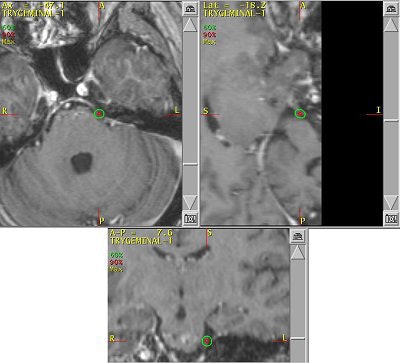

![]() |

| An example of a treatment plan for TN using a single isocenter to deliver a single fraction of 80 Gy to the TN nerve root. A single 5-mm collimator and a multiarc technique would be used to minimize dose to the brain stem. Image courtesy of Varian Medical Systems, Palo Alto, CA. |